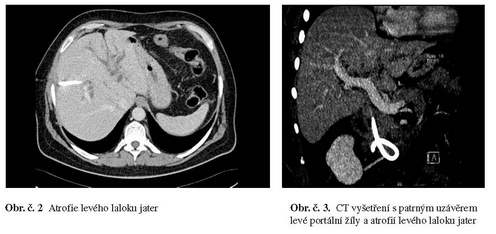

Nález byl chirurgem na jiném pracovišti vyhodnocen jako inoperabilní, z provedené peroperační biopsie nebyl histologicky karcinom potvrzen, přesto byla provedena brachyterapie cestou PTD, při které byla rovněž zavedena trvalá zevní drenáž jater. Na CT vyšetření je zřejmá atrofie levého laloku jater v důsledku postižení a uzávěru levé portální žíly. Obr. č. 2,3.